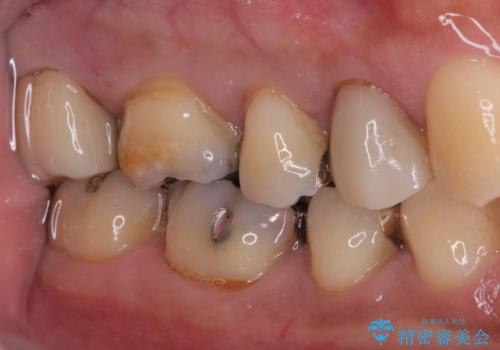

【フルジルコニアクラウン】銀歯二次カリエス!

今回も不適合な銀歯を外したらその下は虫歯になっていました。

虫歯を除去後、フルジルコニアクラウンで治療を行いました。

不適合な銀歯を外して、虫歯の除去後にシリコンで印象をとりフルジルコニアクラウンで治療を行いました。